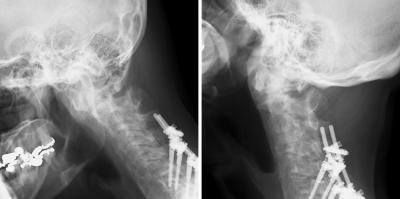

२०-२५ मिनिटांनी रक्तांचा पुरवठा इतका कमी होतो की, त्यामुळे रक्ताची गुठळी तयार होते. त्यामुळे स्ट्रोक सारखी स्थिती येते त्याला ब्यूटी पार्लर स्ट्रोक सिंड्रोम म्हटलं जाते. या महिलेसोबत असेच झाले आहे. मान मागच्या बाजूस जास्त वेळ ठेवल्याने रक्ताची गुठळी तयार झाली.